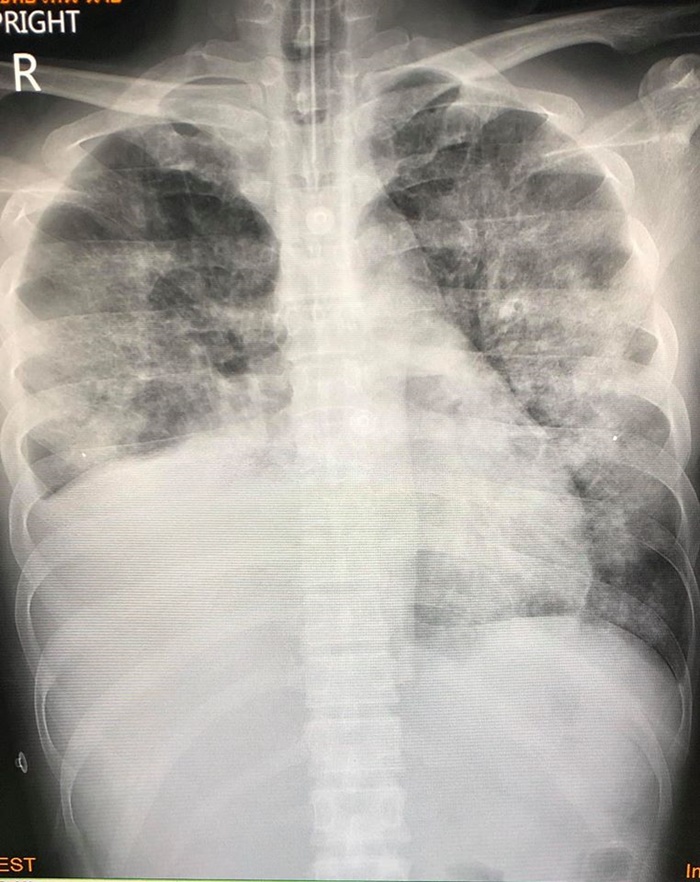

อาการไม่ดีขึ้น เมื่อเอกซเรย์ปอดก็พบว่ามีฝ้าขาวทั้งสองข้าง

ส่วนปอดเดิมที่เป็นมะเร็ง ก็พบว่าก้อนมะเร็งมีขนาดใหญ่กว่าเดิม

เมื่อส่งตรวจทางห้องปฏิบัติการก็วินิจฉัยได้ว่าเป็นปอดอักเสบจากการใช้กัญชาด้วยบุหรี่ไฟฟ้า